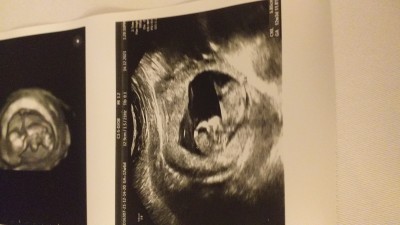

image

Erkek geçti içimden

Kuş diyorum ben

Aaa kuş ne ay :D kız kuzum evet

Kız gibi geldi canm hayırlı evlat olsun inşallah sağlıkla kucağına alırsın<3

Kiz bence oyrenince soyle bakalim neymis saglikli olsunda canim